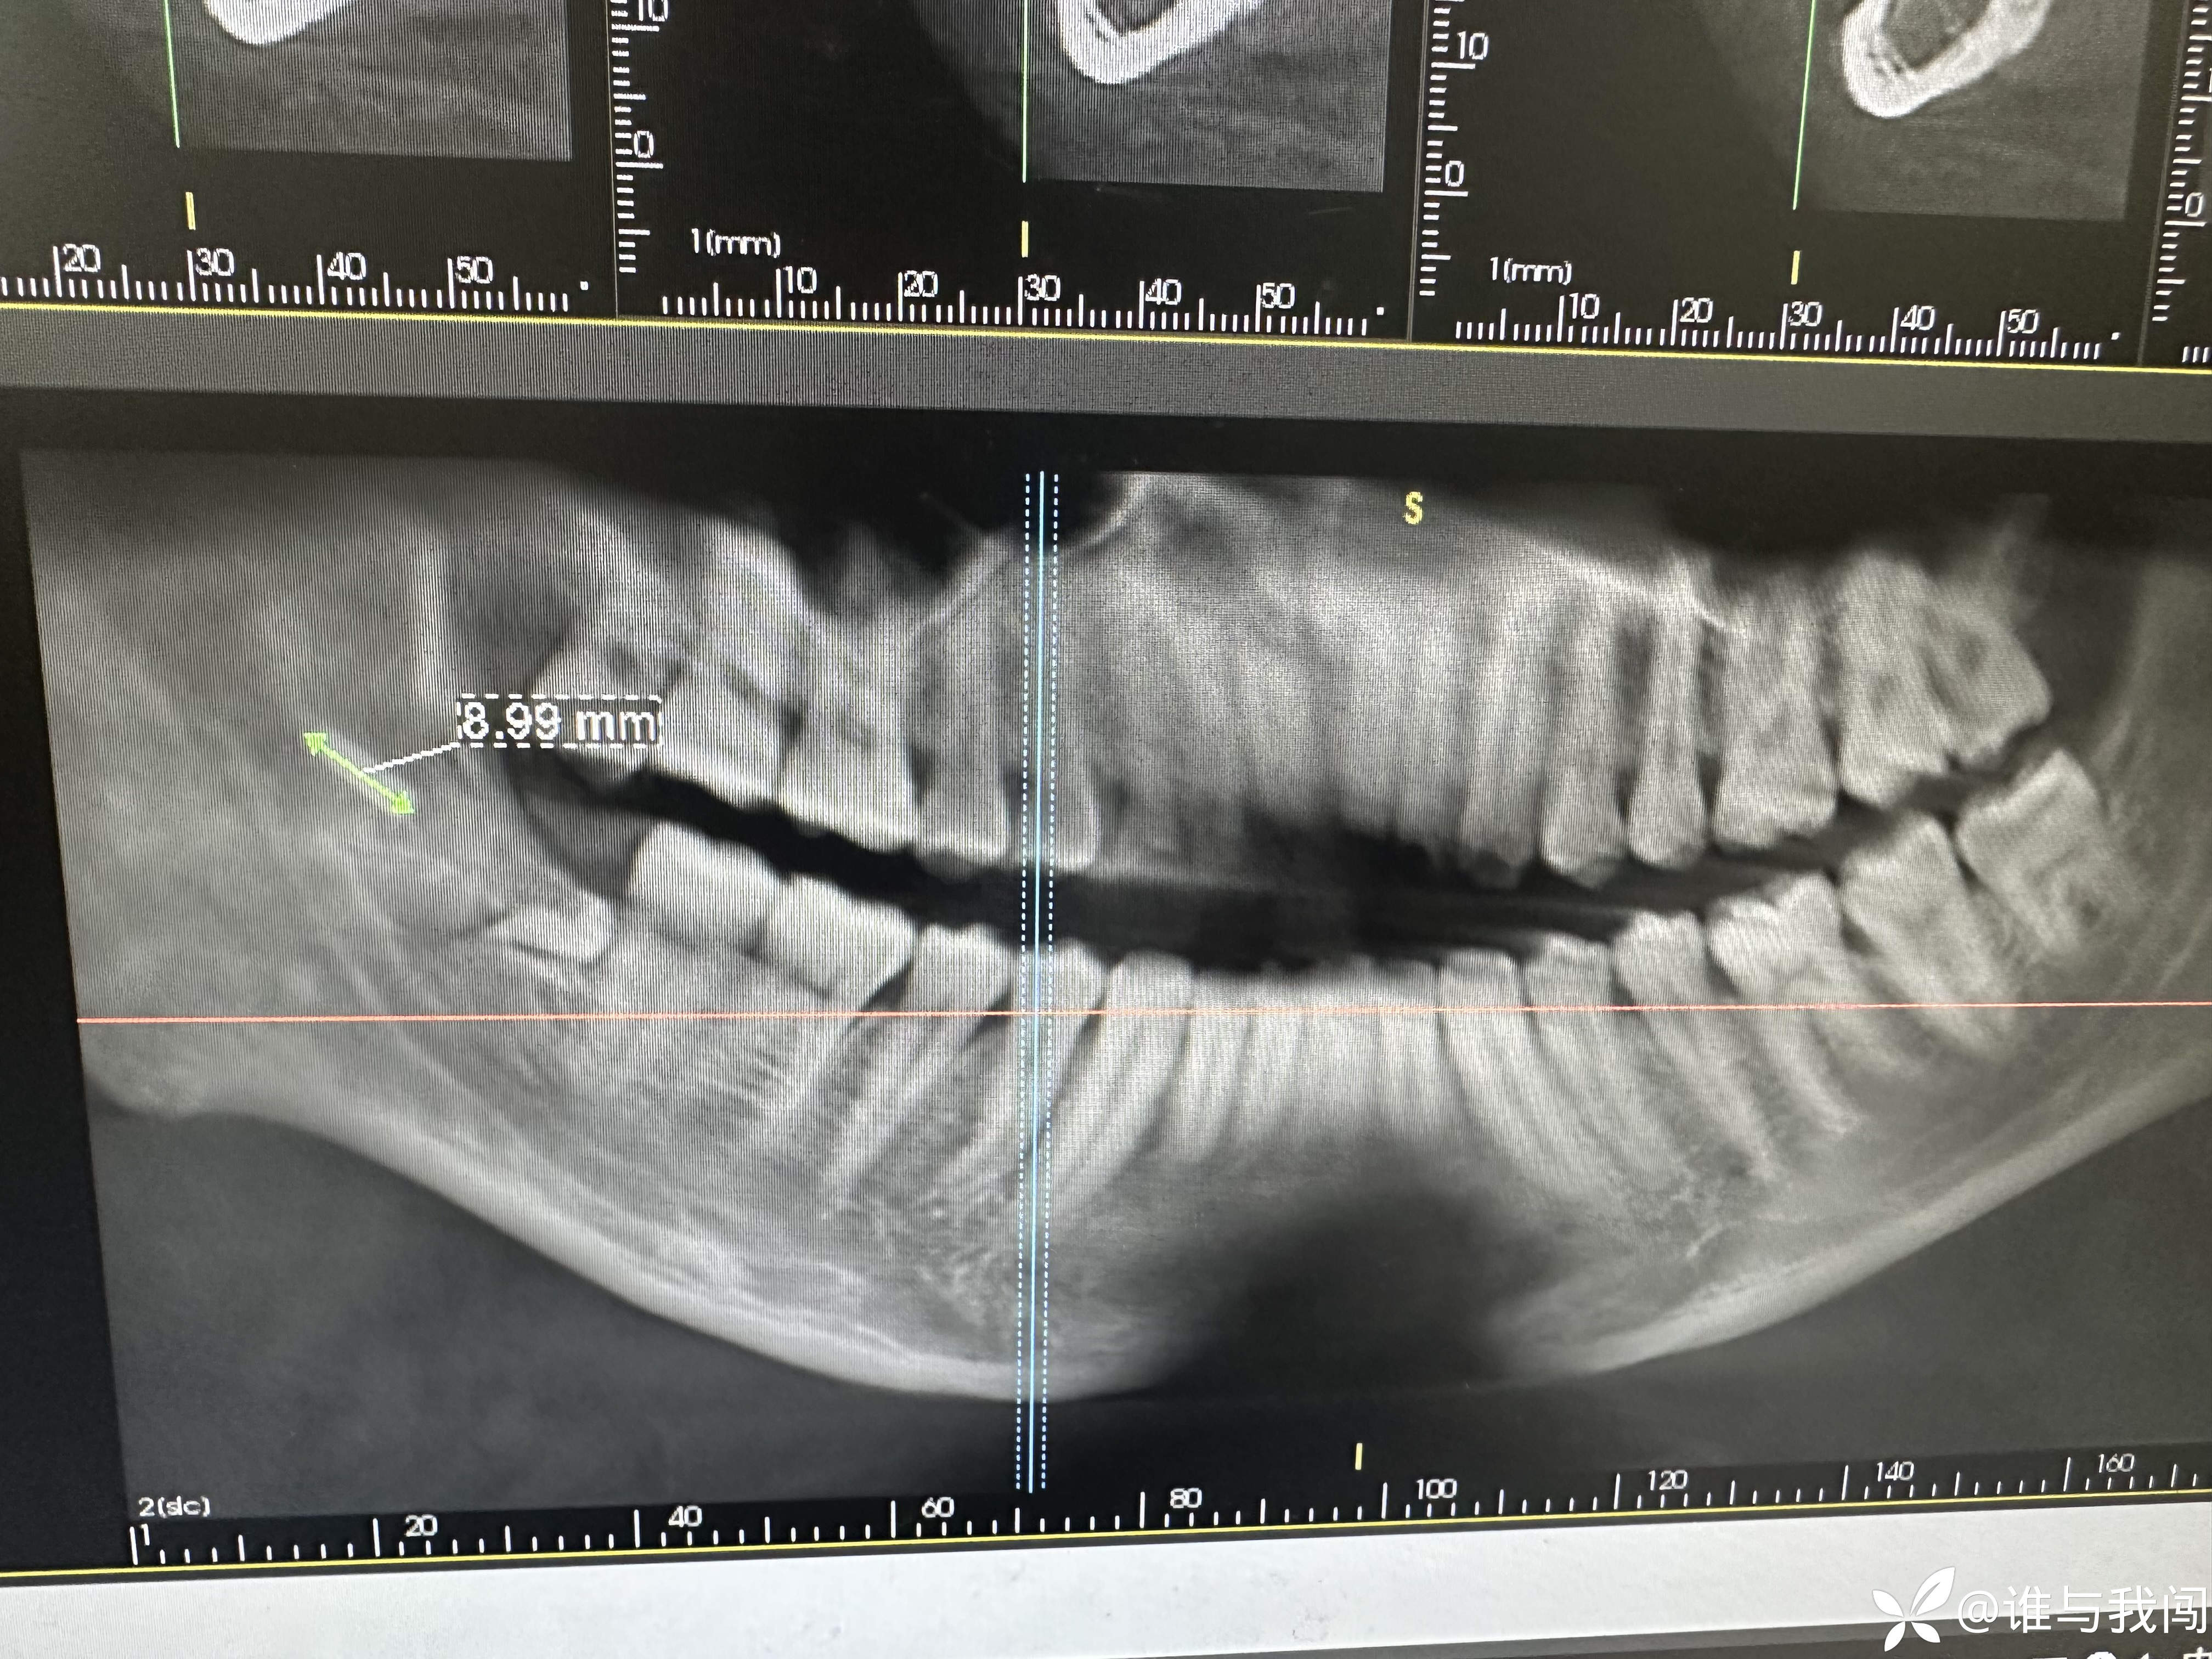

患者是从我们医院另外一个院区过来的,48阻生齿拔除,带过来的时候说是牙挺断在里面了,拍ct看有一个近9mm的样子,是另外一个院区一个老医生拔的。